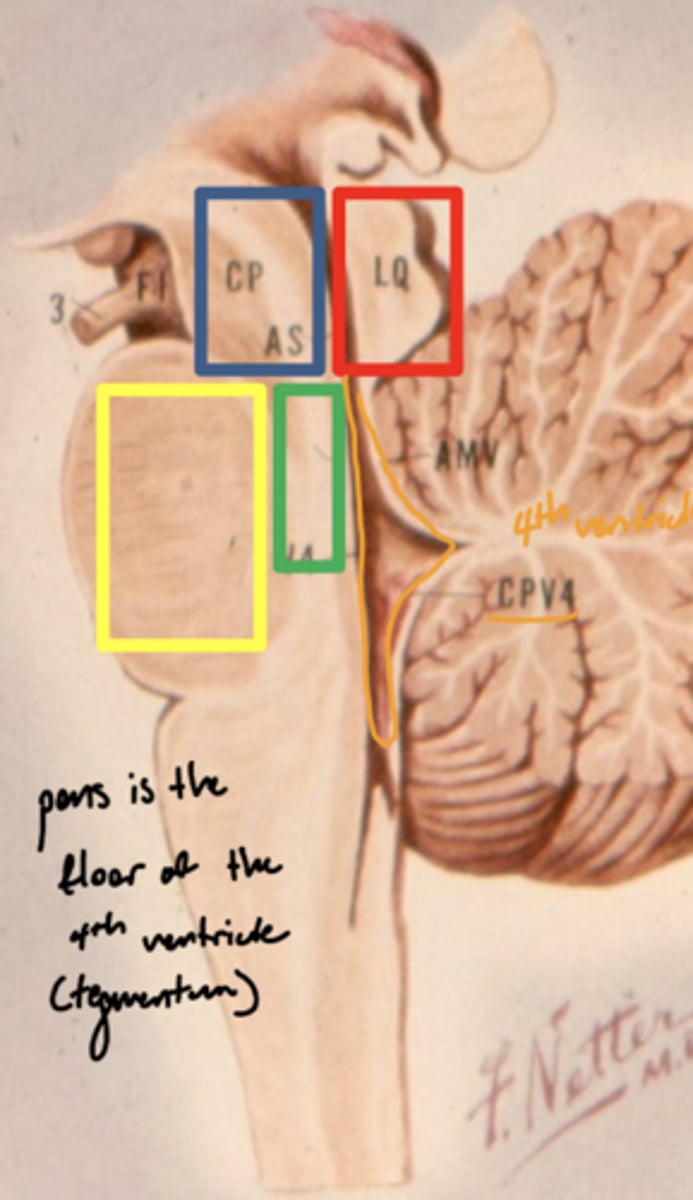

What is the floor of the 4th ventricle?

tegmentum pons

image -- green

What is the dividing line between the tegmentum pons and the base of the pons?

trapezoid body -- decussating auditory fibers

What is the superior medullary velum?

membrane that forms the superior portion of the 4th ventricle roof

image -- 7

What is the inferior medullary velum?

membrane that forms the inferior portion of the 4th ventricle roof

image -- 1

What structures does CN V divide ventral to dorsal in the pons?

base of pons from middle cerebral peduncle

ventral -- base of pons

dorsal -- middle cerebral peduncle